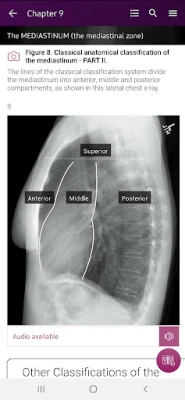

Section II* introduces the concept of radiological zones to give you a starting point in the understanding of the radiological anatomy of the chest. The next chapters review in detail the radiological anatomy of specific anatomical structures, also provide examples of how the x-ray image can change due to pathology. The final chapter explains how the individual structures come together to form the radiological image.

Radiological Anatomy – Descriptions of various anatomical structures as they would appear on PA and lateral chest x-rays.